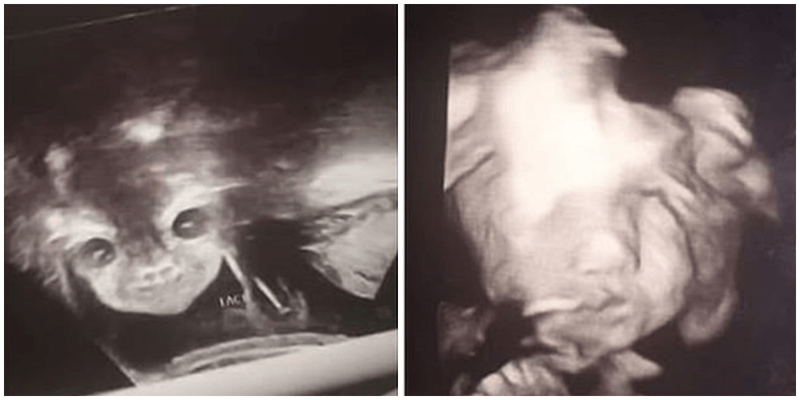

Айанна Кэррингтон, будучи на 24 неделе беременности, отправилась на УЗИ, чтобы узнать пол будущего ребёнка. Когда девушка взглянула на монитор, то пришла в ужас. Ребёнок повернул голову и посмотрел прямо на мать. В это время на его лице была ухмылка, сообщает DailyMail.

Девушка была напугана и удивлена одновременно. Врач поспешила успокоить будущую мать, объяснив, что ребёнок просто повернулся лицом к аппарату. Такое случается довольно часто. После УЗИ специалист обрадовала Айанну, сказав, что она ждёт дочку.

“Я никогда не видела ничего подобного, просто хотела узнать, мальчик это или девочка. Но я уже очень сильно люблю этого “дьявольского ребёнка” – написала девушка в Twitter.